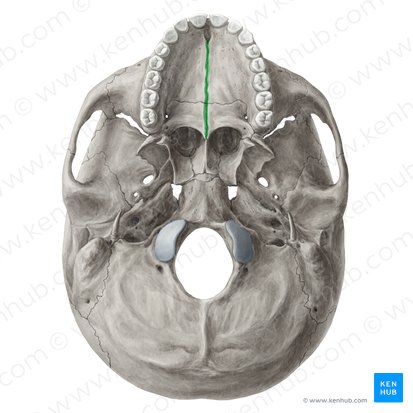

| maxilla | intermaxillary suture

| palatomaxillary suture